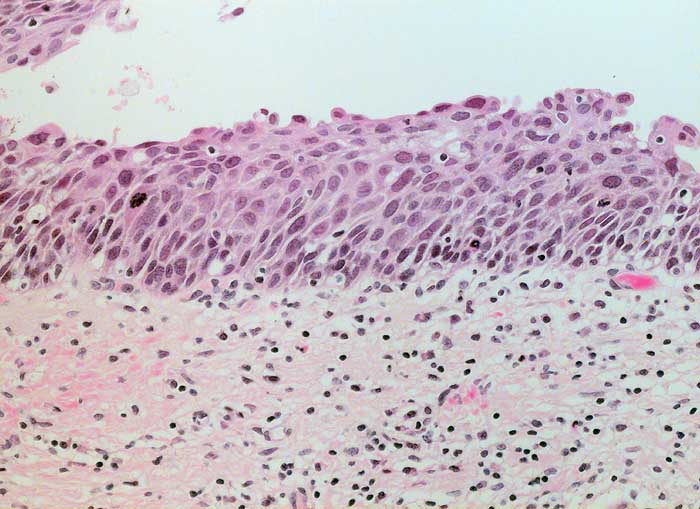

PathoPic ID 6209 - schwere Dysplasie CIN III

schwere Dysplasie CIN III

Portio

Portiokonisat: Auf der gesamten Epithelbreite atypisches Epithel ohne Ausreifung.

Weitere zytologische Kontrollen unverdächtig.

Histologie

200